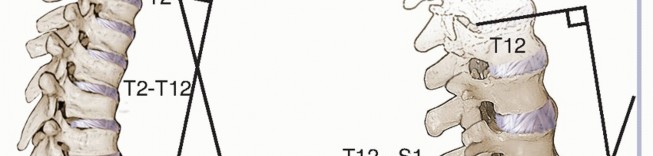

*FIG 6 • Regional lordosis and kyphosis are measured on the standing lateral radiograph. Typically, the vertebral endplates are used as **

*FIG 6 • Regional lordosis and kyphosis are measured on the standing lateral radiograph. Typically, the vertebral endplates are used as **